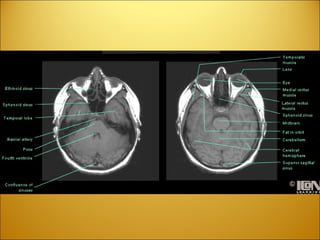

Dura mater (reflections) Crista galli  Falx cerebri  Sinus sagittalis inferior  Incisura tentorii - Tentorial incisure  Sinus rectus  Confluens sinuum  Tentorium cerebelli  Sinus petrosus superior  Sinus sphenoparietalis  Diaphragma sellae  Arteria carotis interna  Nervus opticus  Foramen magnum

Dura mater (reflections)Crista galli Falx cerebri Sinus sagittalis inferior Incisura tentorii - Tentorial incisure Sinus rectus Confluens sinuum Tentorium cerebelli Sinus petrosus superior Sinus sphenoparietalis Diaphragma sellae Arteria carotis interna Nervus opticus Foramen magnum